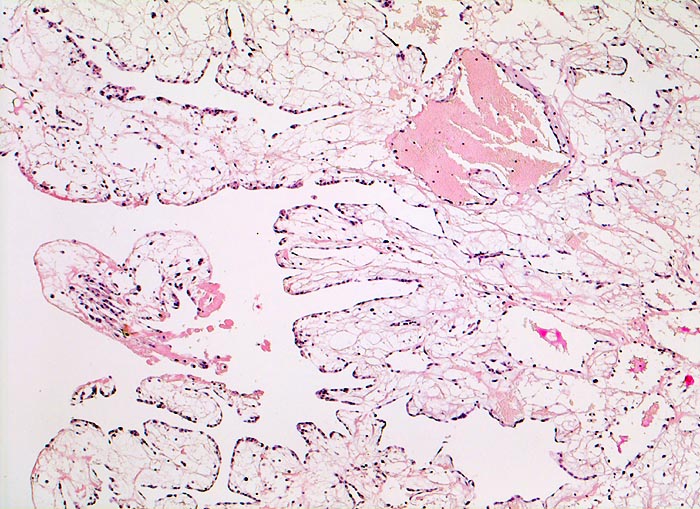

AP/ Vorhofmyxom

Vorhofmyxom

Herz Vorhof